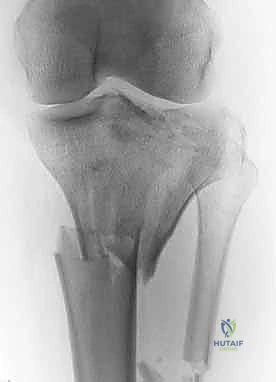

2. التصوير الإشعاعي (X-rays)

الخطوة الأولى هي التقاط صور أشعة سينية من عدة زوايا (أمامية خلفية، وجانبية). تعطي الأشعة السينية فكرة عامة عن وجود الكسر وموقعه، لكنها غير كافية لتقييم الكسور ثنائية اللقمة المعقدة.

كسر الهضبة الظنبوبية ثنائي اللقمة (Bicondylar Tibial Plateau Fracture) هو إصابة عظمية شديدة الخطورة تؤدي إلى انفصال وتفتت كلا السطحين المفصليين (الإنسي والوحشي) عن الجذع الرئيسي لعظم الساق (Diaphysis). يعني مصطلح "ثنائي اللقمة" أن خطوط الكسر تمتد عبر المفصل بأكمله، مما يفصل الركبة فعليًا عن بقية الساق من الناحية الميكانيكية.

هذه الكسور تُصنف كحالات طوارئ أو شبه طوارئ في جراحة العظام، حيث يفقد المفصل استقراره تمامًا، وتتعرض الأنسجة الرخوة المحيطة (الجلد، العضلات، الأوعية الدموية، والأعصاب) لتهديد مباشر نتيجة التورم الشديد وحركة الشظايا العظمية الحادة.

| النوع الخامس (Type V) | كسر ثنائي اللقمة (Bicondylar). انشطار كلا اللقمتين الإنسية والوحشية. | موضوع مقالنا. المفصل مفصول عن جسم العظم. يتطلب تثبيتًا مزدوجًا (ألواح من الجهتين). |

| النوع السادس (Type VI) | كسر ثنائي اللقمة يمتد إلى الجذع الرئيسي للساق (Metaphyseal-Diaphyseal dissociation). | الأكثر تعقيدًا وتدميرًا. انفصال كامل للمفصل عن الساق. تورم هائل وخطر شديد على الأنسجة الرخوة. |